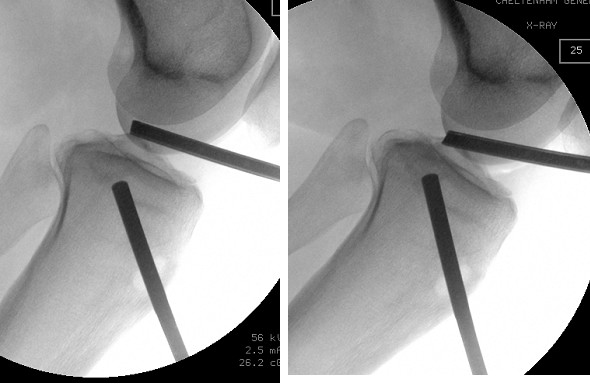

The subtle depressed fractures can be treated arthroscopically with percutaneous placement of screws.